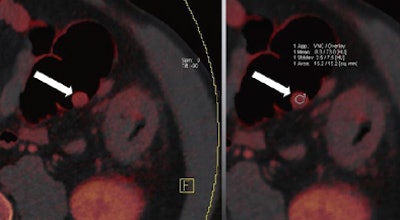

| Images are of a 65-year-old male patient who underwent a single acquisition at dual-source CTC. Above, a stenosing carcinoma was seen in the proximal sigmoid colon in 3D endoluminal views (left, middle) and 2D view (right). Below, an 18-mm colorectal adenoma was also found in the proximal sigmoid colon, and also appears to be enhancing. Bottom image shows an enhancing liver metastasis in the same patient. Virtual unenhanced (grayscale) images are created by electronically subtracting the contrast media. All images courtesy of Dr. Anno Graser. |

The technique can be used to determine the contrast media uptake of the polyp, as well as the baseline density of the lesion, directly measuring enhancement in HU and measuring the iodine in the lesion in grams per mL.

The mean enhancement of adenomas was 55 ± 27 HU.

The mean enhancement of hyperplastic lesions was 13 ± 10 HU.